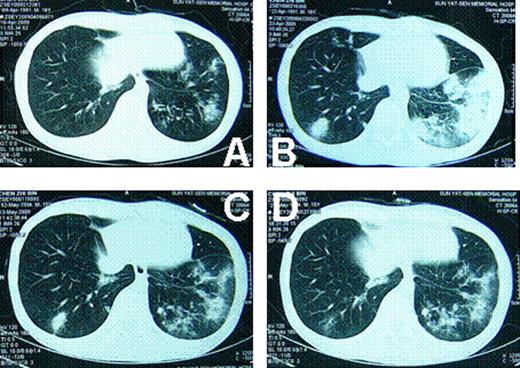

At the onset of the pulmonary diseases, anti-GVHD drugs (Including prednisone, CsA) were already withdrawn for both cases. There was no GVHD progression after withdrawal of the anti-GVHD drugs. Both cases had fever, ranging from 38 to 39 centigrade. Patients were short of breath. Oxygen inhalation was needed. Case 1 was in severe hypoxia. The oxygen saturation was down to 70%∼80% at the peak severity. Neither of the 2 cases was in need of mechanical ventilation. CT images showed that these 2 cases had similar lung injuries (Fig 1 and Fig 2). Tissue biopsy revealed that different pathogens were involved in these 2 cases, although they had identical disease history, similar duration after transplantation, same clinical symptoms and signs, even similar CT images. The histological findings of lung biopsies showed that the pathogen for case 1 was aspergillums, whereas that of case 2 was tubercle bacillus. Both cases responded well to the specific treatment, respectively. Patients are now in disease-free state.

Both tuberculosis and fungus infection could show diffused foci on CT image. The diffused lesions of tuberculosis tend to fuse, whereas little cavities were more frequently seen in fungus infections. After treatment, the lesions of fungus were much easier to be clear than tuberculosis. Diagnostic treatment might be used to distinguish these 2 diseases if biopsy cannot be performed or pathogen culture is negative.

lung CT of case 1. A: when the pulmonary infection began; B: 2 weeks later; C: 5 weeks later; D: 7 weeks later.